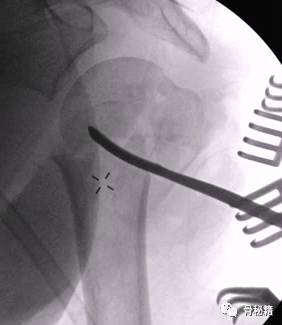

解剖钢板与提拉螺钉的复位

需要注意 不要应用过度提拉 使得内侧肱骨距过复位

注意完成内侧支撑和内外翻的复位

在此病例中,为了复位良好,舍弃了肱骨近端与钢板贴服